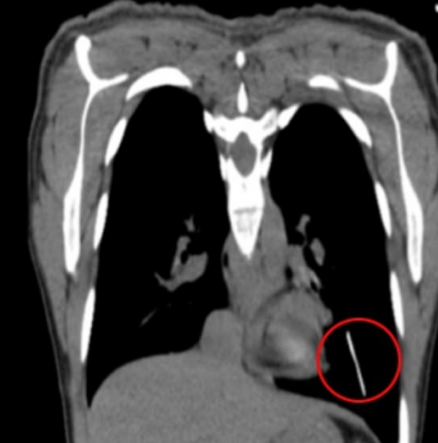

The gynecology department of the hospital had conducted tests on her after her doctor could not find the device where it should have been. To find the device they conducted tests and found it out at the bottom of the left lung in the woman’s body.

The doctors said that over a period of time the device must have moved from its place and occasionally, through the arteries and the veins would have ended up reaching the lung.